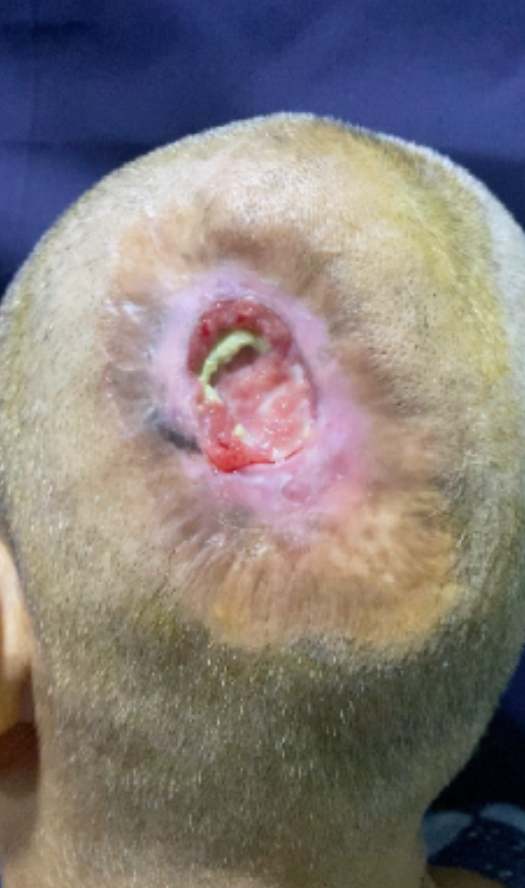

REPLANTATION

SCALP RECONSTRUCTION

Sensitive Content

This media contains sensitive content that some viewers may find disturbing.